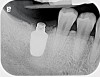

Fig 16. Radiograph depicting closed contact at time of implant insertion.

Figure 16

Fig 17. Open proximal contact between implant and adjacent tooth 3 years post insertion.

Figure 17

During the initial planning phase for implant therapy, the dental practitioner should not assume that the existing position of the teeth within the dental alveolus will remain stationary throughout the patient’s lifetime. Long-term follow-up of implant restorations has proven that often it does not remain stationary, regardless of the age of the patient. Open contacts have frequently been reported between implants and adjacent teeth.30

Open proximal contacts between implants and adjacent teeth have been attributed to ongoing craniofacial growth31 and vector forces mesializing tooth position (Figure 16 and Figure 17).32 These changes, particularly in the esthetic zone, can contribute to differences in incisal edge position, gingival margin height, and the facial contour and alignment of the dental arch (Figure 18 and Figure 19).31 Jemt et al30 studied a population of 28 consecutive anterior implant crowns followed for 15 years. During this time, only 8 patients demonstrated no movement of the adjacent teeth; 55% of adjacent teeth displayed palatal tooth movement, predominately in the female population.30 Shifting of teeth can contribute to occlusal changes leading to uneven occlusal load and distribution among the arch.31 Similar to adjacent open contacts between teeth, any open contact can lead to food impaction/accumulation, pocketing, and inflammation of the interdental tissue.